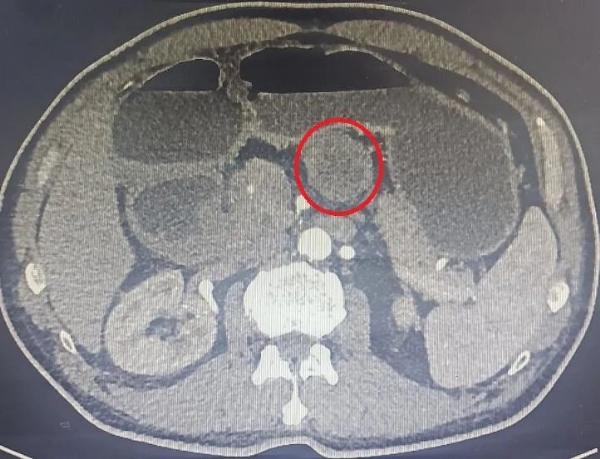

近日,我院外三科顺利完成了2例胃肠道间质瘤手术。其中一例为腹腔镜下胃间质瘤切除术,第二例为小肠间质瘤术后复发,再次手术切除。案例一:一个月前,70岁的陈先生因恶心、呕吐伴呕血前往我院就诊,经胃镜以及腹部CT发现,胃体小弯侧后壁有个直径5cm大小的肿瘤,考虑胃间质瘤可能性大。金鑫主任团队采用腹腔镜下胃间质瘤切除,这种微创的手术方式仅仅需要5个0.5—1.2厘米大小的小孔即可将肿瘤从胃上完整切除,相较于传统手术,其创伤更小、恢复更快、痛苦更少。手术顺利,术中无明显出血,术后确诊为胃间质瘤(中度风险),现已顺利出院。患者及家属对此次手术效果表示非常满意,切实体验到微创手术相比传统开腹手术的优越性。

腹部CT检查所示: